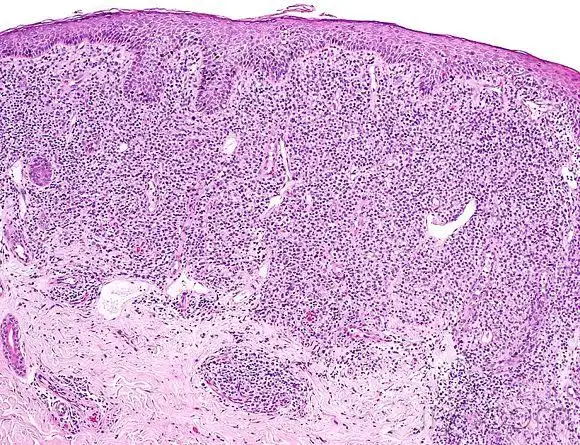

皮肤临床病理08蕈样霉菌病